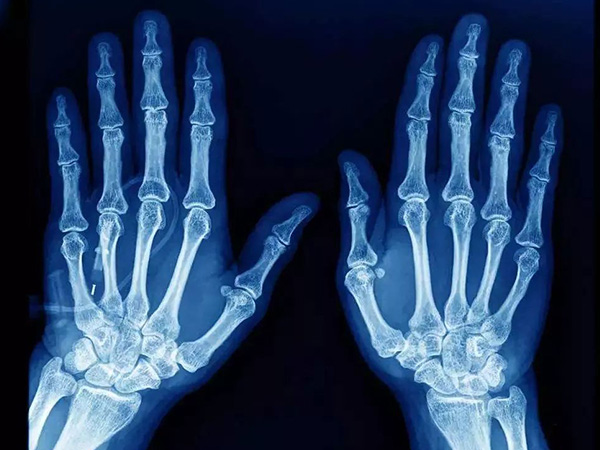

x射线无法穿透金属

虽然在排x光的时候对患者的穿着有一定的要求,但这种要求只是基于检查仪器而言的,就普通的衣服来说是不会干扰到拍x光的效果的,更不需要到脱光的地步。

在拍胸片时,注意叮嘱患者前胸后背不要佩戴金属饰品,或者将金属类的小物品以及硬币等等放在上衣口袋里。衣服上不能有铁扣、塑料扣、领带夹以及女士内衣中的铁圈、内衣扣等等,以避免片子上会出现伪影,阻挡病灶。

拍胸片时要穿着简洁,便于脱下,衣服上不要镶嵌饰品,以免影响诊断。另外,在拍片时要求患者要保持呼吸规律平稳,在有条件的情况下,尽量使用铅衣来保护病人的生殖系统。